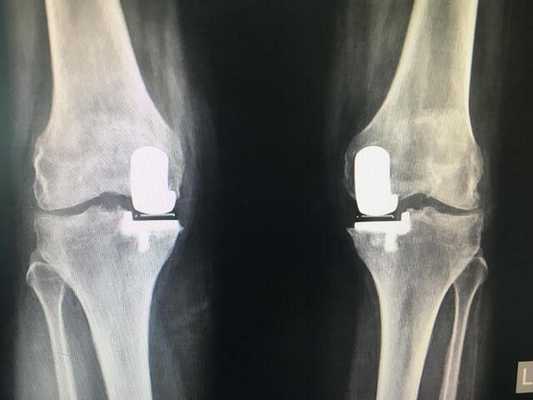

- - протезированию подлежит только одна из полукруглых возвышенностей бедренной кости с подлежащим к ней проксимальным фрагментом большеберцовой кости (применяется у пожилых пациентов и у лиц с низкой физической активностью);

- тотальная операция (полная) - меняется весь коленный сустав, он удаляется полностью, а на его место имплантируется эндопротез;

Неполные имплантаты, устанавливаемые при частичной замене, имеют короткий срок эксплуатации. Такие модели вырабатываются в 2 раза быстрее, чем тотальные конструкции, при этом их потенциал прочности не рассчитан на высокой степени физические нагрузки. Преимущества частичного протезирования состоят в том, что замещается имплантатом только определенная часть сочленения, остальная область остается нетронутой. Таким образом, щадящее вмешательство позволяет сократить сроки реабилитации и перенести восстановительный период относительно легко.

Две техники операции у одного пациента.

Вы уже знаете, что бывает полное и частичное эндопротезирование коленного сустава, где в первом случае лечение подразумевает полноценную замену суставных поверхностей, а во втором - имплантацию поврежденного участка одного из мыщелков. Соответственно, протезы классифицируются на тотальные, одномыщелковые и ревизионные для замены импланта.

- После постановки однополюсной системы максимально сохраняется собственный костно-хрящевой сегмент и не затрагиваются связки, кстати, они должны быть в хорошем состоянии.

Одномыщелковая замена сустава на рентгене.

Сравнение двух типов операций.

Одномыщелковое протезирование подразумевает срок службы небиологического устройства максимум 7 лет. Тотальное замещение предусматривает время службы вживленного механизма от 15 лет. Ревизионное переносится сложнее, а риск инфекции и других негативных явлений почти в 2 раза выше, чем после первичной операции.